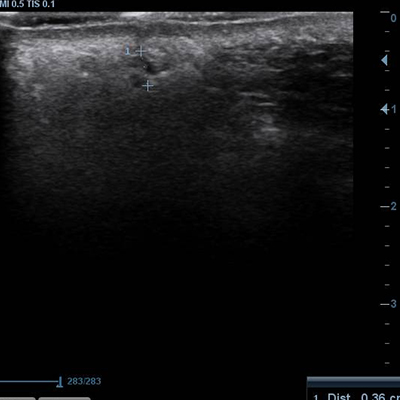

[얼굴이물질제거] 17.02.19 - 이물질제거(매선) - 전후사진

17.02.19 - 이물질제거(입술) - 전후사진